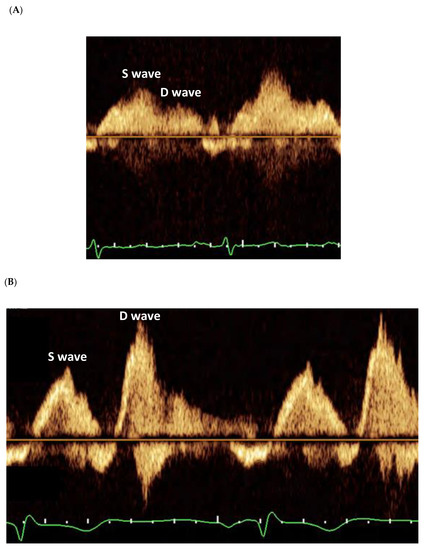

3.2. Pulmonary Venous Flow Pattern